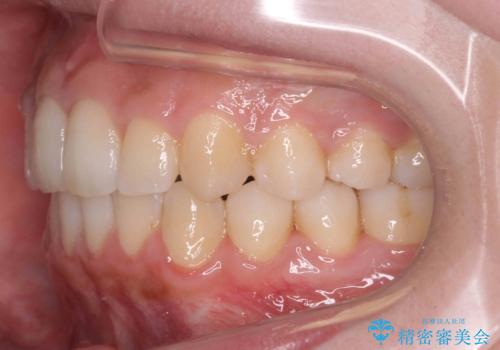

- ワイヤー矯正

- 2年11ヶ月

上の歯を全体に大きく後ろに下げる治療計画を立てました。